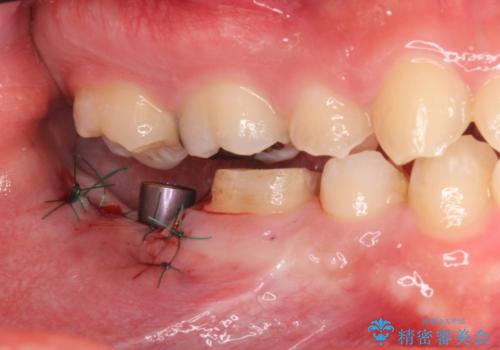

抜歯したところは抜歯後骨の治癒を待ち、CTを撮影しインプラント治療ができる事(骨の厚みなど)確認し治療を行いました。

白くて綺麗な被せ物が入りました。

インプラントを入れた後は定期的なメンテナンスが必要になります。